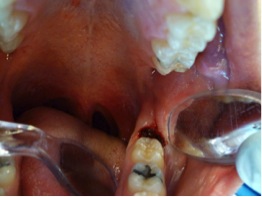

Fig 9. The ablation of the inflamed tissue began.

Figure 9

1. Anesthesia was administered by the local infiltration technique: 2% lidocaine with 1:100,000 epinephrine; a 30-gauge needle was used (Figure 7).

2. The angled handpiece of the CO2 laser was held perpendicular to the target lesion (Figure 8) and the ablation of the inflamed tissue began (Figure 9). The dental surgeon was careful to avoid contact between the laser beam and the tooth enamel. (Note: In this case, the inflamed tissue was located distally from the involved molar. There was no direct contact of the beam with the tooth, as the surgeon was careful not to hit the enamel. However, if an operculum covers part of the tooth, an adaptive tool (for example, a wax spatula) needs to be inserted between the tissue and the tooth to prevent possible damage. For an inexperienced CO2 laser surgeon, it is important and highly recommended to always shield the tooth during the procedure.6)